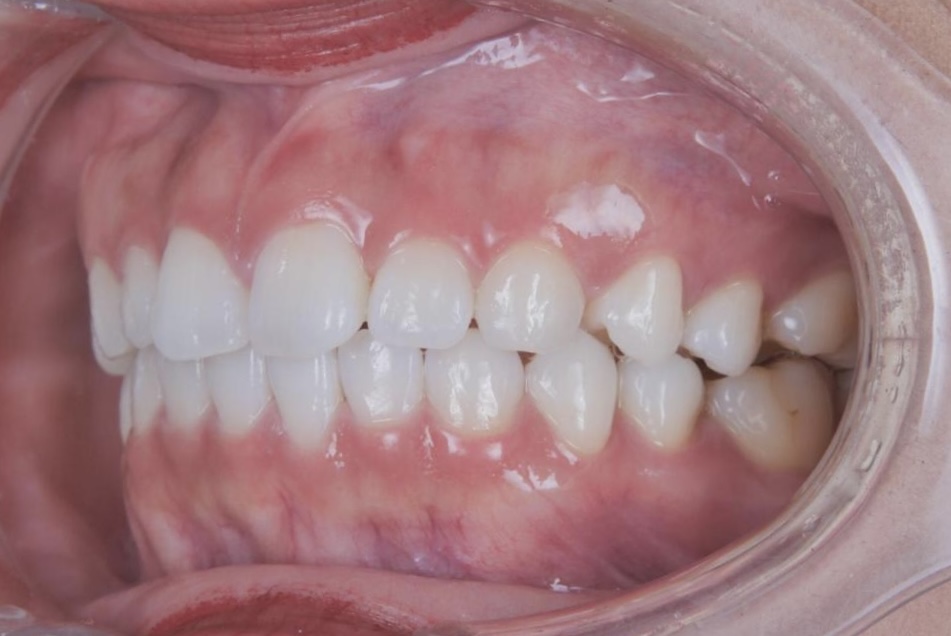

AFTER

治療はマウスピース矯正で行い、治療期間はわずか1年で歯並びが整いました。さらにホワイトニングも併用したことで、歯並びだけでなく歯の色も明るくなり、整った歯並びと白い歯が調和した、より印象的な口元へと改善しています。

治療後は、周囲の方から歯を褒められることが増え、笑顔に自信が持てるようになったとお話しくださり、「本当に矯正してよかった」と、現在もメインテナンスで通院されるたびに嬉しいお言葉をいただいています。また、お子さまのうちお二人も、同じマウスピース矯正で現在当院にて治療を進めており、ご家族で通っていただいている症例です。